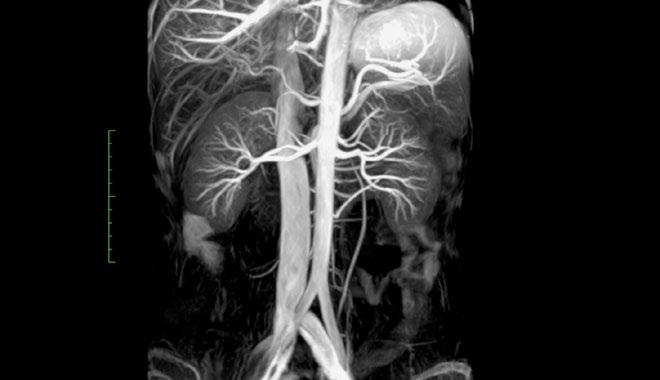

GHUPPN will evaluate specific MR sequences for brain tumor and acquire a better understanding of the evolution of brain gliomas by deeply analyzing their spatial organization and get a better delineation between tumors and surrounding benign brain parenchyma. A second research priority is to develop and evaluate contribution of contrast-free MR angiography for head and neck vessels and compare to current gold-standard MR angiography with contrast-media injection. Leveraging its extensive expertise in Psychiatry, GHUPPN is also planning to use the Vantage Galan 3T/ Saturn X Gradient to evaluate the contribution of dedicated MR pulse sequences for children and teenagers with psychiatric disorders and cognitive development limitation.

Patient comfort

To maximize patient comfort, the Vantage Orian 1.5T has a 71 cm wide bore, is equipped with Pianissimo and has options like MR Theater and dedicated free breathing and contrast free sequences to ensure easier examinations for every patient.

An increasing awareness of the potential risks associated with gadolinium-based contrast agents has revealed the need for alternative, contrast-free MR angiography techniques. Canon Medical offers a full range of non-contrast MRA sequences to minimize risk to patients with sensitivity to contrast while producing exceptional diagnostic images. Furthermore, free-breathing images can be acquired using Quick Star or k-t SPEEDER or using navigator-triggered sequences.

With the Encore Upgrade, the customers now have access to the Vantage Orian 1.5T hardware and digital software platform that can help improve workflow and deliver clinical confidence. Depending on the current platform, new options become available like contrast-free MR angiography, ultrashort echo time (UTE) imaging and Water Fat Separation (WFS), a technique that provides homogenous fat suppression while acquiring four different tissue contrasts in one scan.